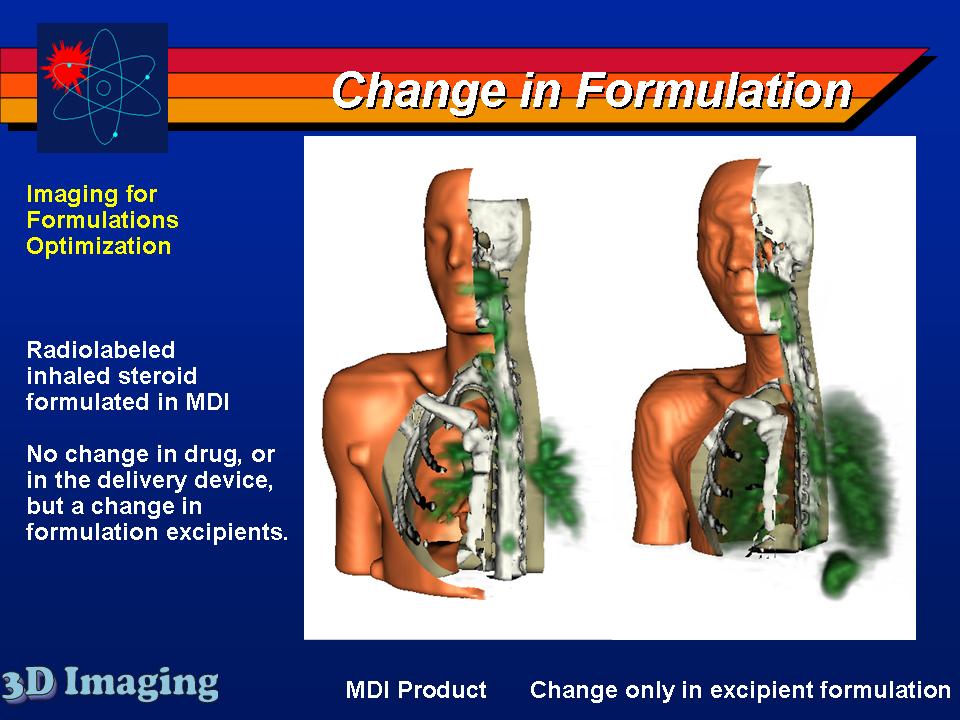

Several inhaled drug formulations were studied by radiolabeling the active ingredient (several different steriods) with C-11 or F-18, formulating that ingredient as the dosage form (different MDI, DPI, and nebulizer formulations), and performing quantitative PET studies of the regional biodistribution and kinetics.

Click on images to see additional examples, larger versions, and videos.